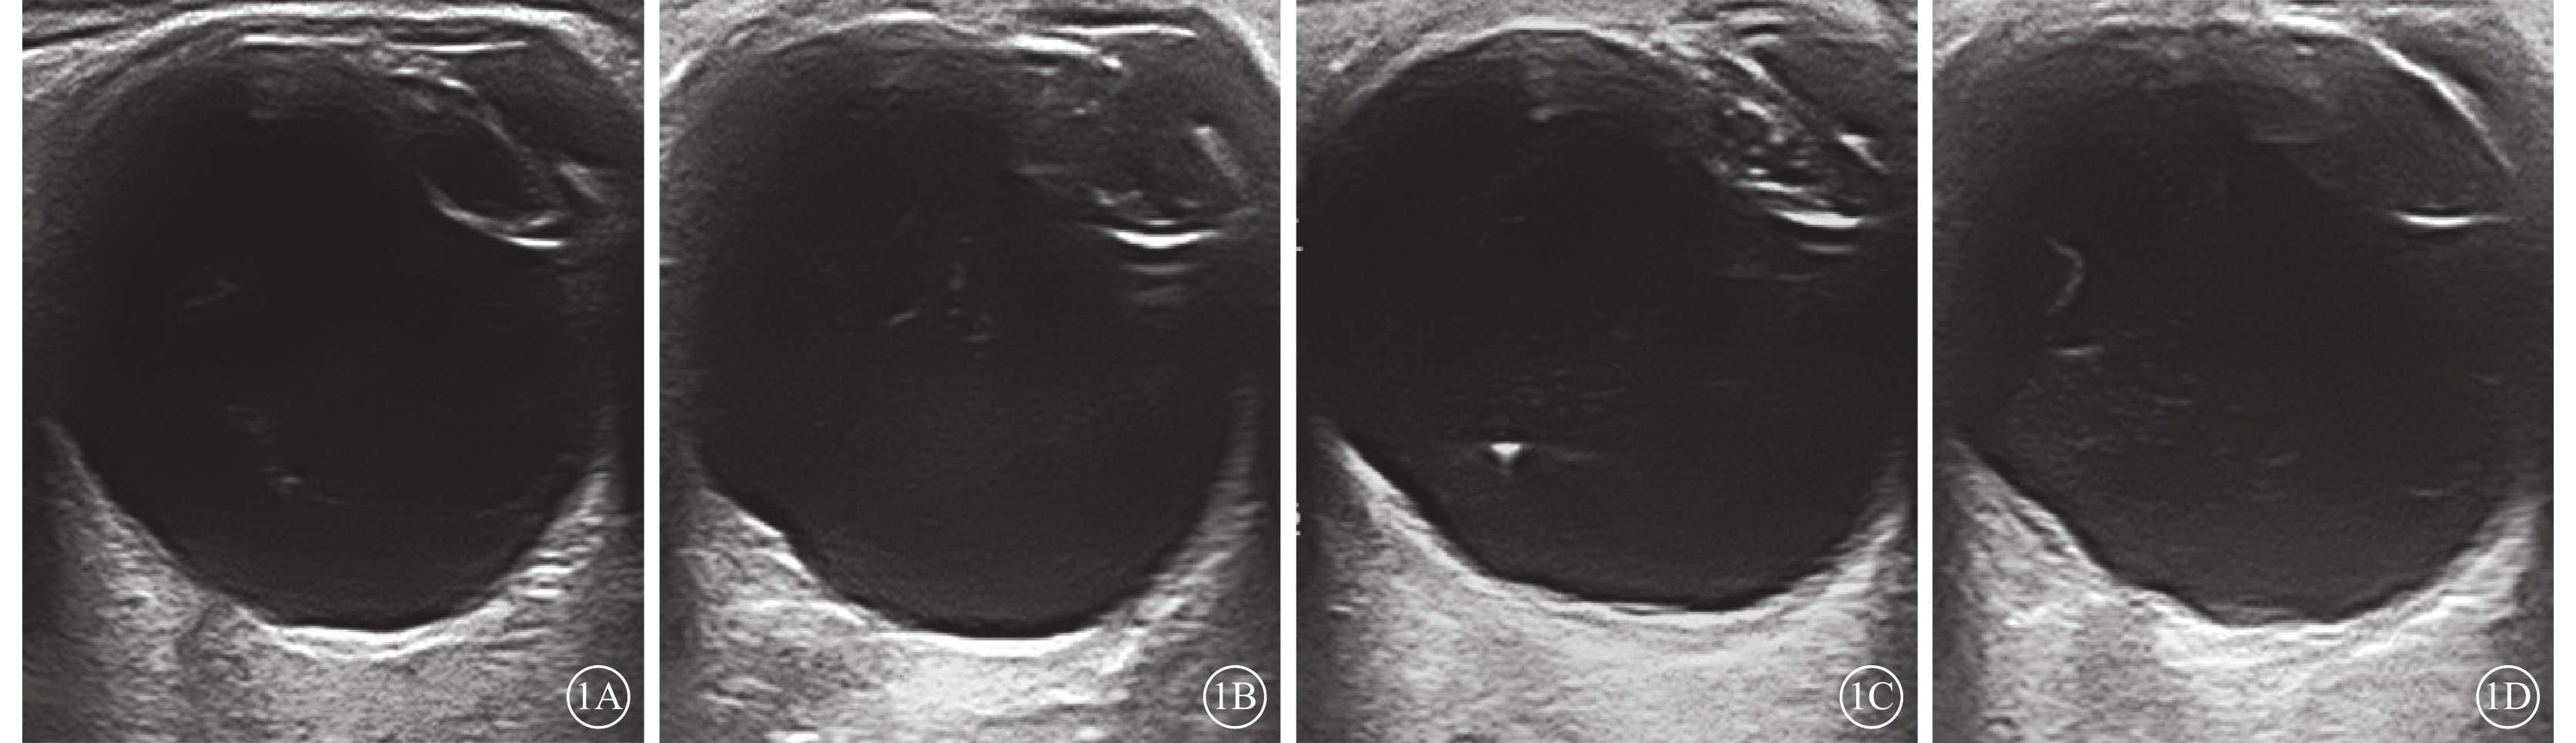

CDFI檢查結果顯示,1380只眼中,發現黃斑區異常回聲164只眼(11.9%)。異常超聲影像表現主要為:黃斑區球壁前膜狀回聲(圖1A)94只眼(6.8%);黃斑區球壁回聲局限隆起(圖1B)33只眼(2.3%);黃斑區球壁回聲增厚(圖1C)23只眼(1.7%);黃斑區球壁可見淺間隙(圖1D)11只眼(0.8%),其中病變表面探及血流信號8只眼(0.5%)。164只眼的平均CFT、AT分別為(393.75±138.47)、(323.64±50.41)μm。

圖1

老年性白內障患眼CDFI像。1A示黃斑區膜狀回聲;1B示黃斑區球壁回聲局限隆起;1C示黃斑區球壁回聲增厚;1D示黃斑區球壁可見淺間隙

圖1

老年性白內障患眼CDFI像。1A示黃斑區膜狀回聲;1B示黃斑區球壁回聲局限隆起;1C示黃斑區球壁回聲增厚;1D示黃斑區球壁可見淺間隙

CDFI檢查結果顯示,1380只眼中,發現黃斑區異常回聲164只眼(11.9%)。異常超聲影像表現主要為:黃斑區球壁前膜狀回聲(圖1A)94只眼(6.8%);黃斑區球壁回聲局限隆起(圖1B)33只眼(2.3%);黃斑區球壁回聲增厚(圖1C)23只眼(1.7%);黃斑區球壁可見淺間隙(圖1D)11只眼(0.8%),其中病變表面探及血流信號8只眼(0.5%)。164只眼的平均CFT、AT分別為(393.75±138.47)、(323.64±50.41)μm。

圖1

老年性白內障患眼CDFI像。1A示黃斑區膜狀回聲;1B示黃斑區球壁回聲局限隆起;1C示黃斑區球壁回聲增厚;1D示黃斑區球壁可見淺間隙

圖1

老年性白內障患眼CDFI像。1A示黃斑區膜狀回聲;1B示黃斑區球壁回聲局限隆起;1C示黃斑區球壁回聲增厚;1D示黃斑區球壁可見淺間隙